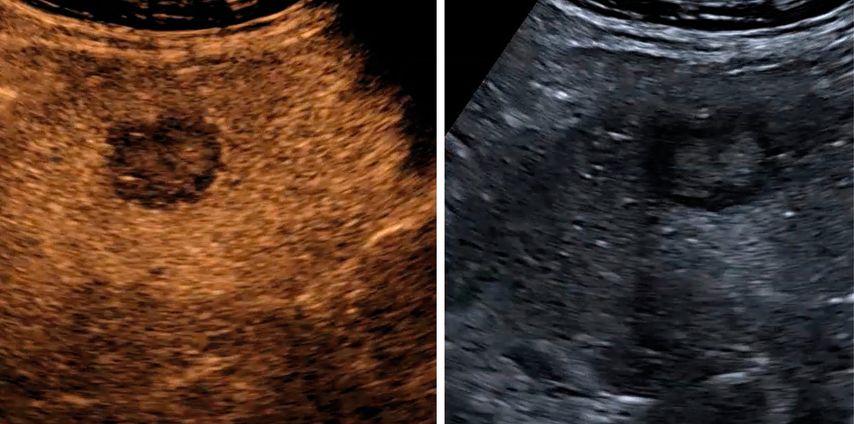

Trotz der hohen Aussagekraft moderner Ultraschallgeräte im B-Mode kann derzeit – mit Ausnahme des Screenings auf hepatozelluläre Karzinome bei chronischen Lebererkrankungen – kein generelles Leberscreening empfohlen werden.5 Die Mehrzahl fokaler Leberläsionen ist benigne, darunter fokale Steatosen, Zysten, Hämangiome oder fokale noduläre Hyperplasien (Abb.3). Maligne Raumforderungen sind in populationsbasierten Studien selten.6

Abb. 3: Darstellung einer fokalen nodulären Hyperplasie (FNH) in der arteriellen Frühphase nach Gabe von 1,2ml SonoVue® mittels CEUS (links) und in der mikrovaskulären Bildgebung (Canon®-superb „Microvascular imaging“-Modus), wo die Radspeichenstruktur besser zur Darstellung kommt